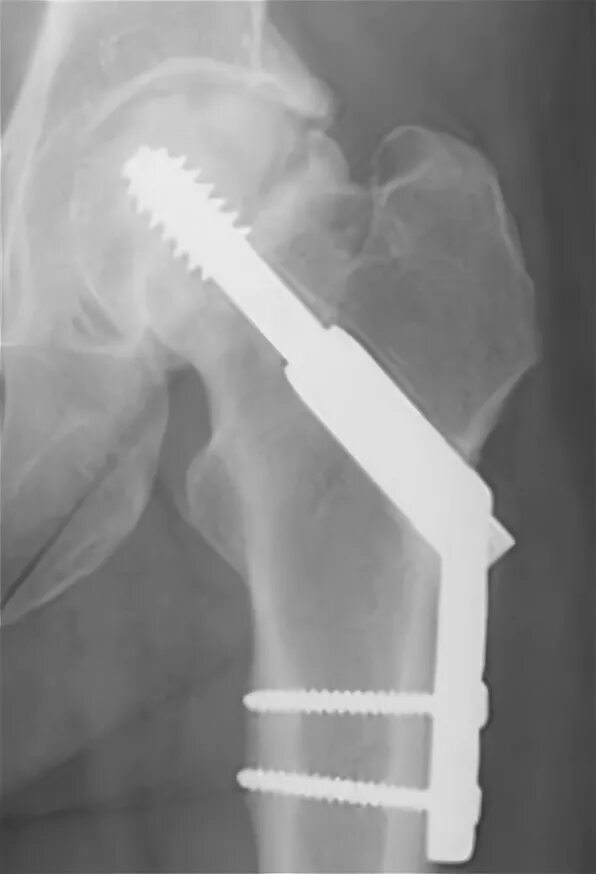

Остеосинтез чрезвертельного перелома